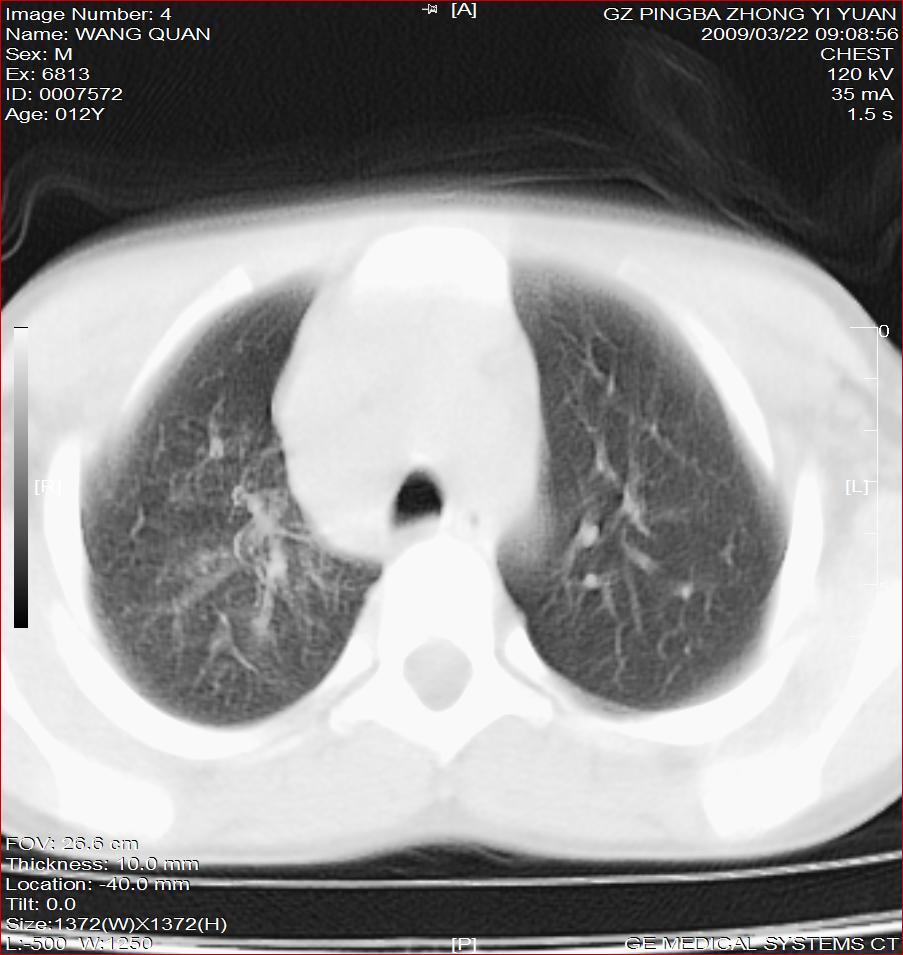

以下是引用随光逐影在2009-3-23 8:12:00的发言:[br]1)右肺门及纵隔淋巴结结核。2)两肺急性血行播散型肺结核可能。3)右侧支气管内膜结核?建议必要时行纤支镜检查。4)右侧少量胸腔积液。